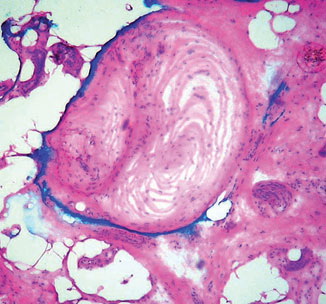

Read MoreVellus hair cysts = كيسات الشعر الزغبي OLYMPUS DIGITAL CAMERA